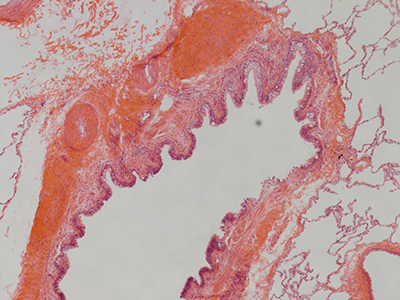

31 Year Old Adult Human Lung DD037 H&E